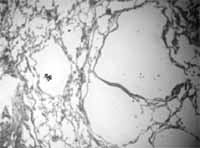

La TAC con cortes de alta resolución, mostró imágenes quísticas parenquimatosas multilobares, con diámetros entre 2 y 5 mm, la mayoría de las cuales, presentaban pared fina ( Figura 2). La revisión de la biopsia pulmonar se interpretó como linfangioleiomiomatosis ( Figuras 3 y 4).

| Figura 3. Biopsia pulmonar. HE 10X .Quistes cuya pared está constituida por músculo liso. | Figura 4. Biopsia pulmonar. 10X . Múltiples quistes. La coloración de tricromo, confirma la presencia de músculo liso en su pared. |

En la TAC de alta resolución, el hallazgo más frecuente es la presencia de quistes, de tamaño variable (2 mm-5 cm), de pared fina, rodeados por parénquima pulmonar relativamente normal, que se visualizan en el 100% de pacientes con linfangioleiomiomatosis.

En ocasiones los quistes no presentan pared definida y su morfología es irregular, lo que dificulta el diagnóstico. La distribución de los quistes es difusa, sin predilección por ninguna zona del pulmón y aumenta con la progresión de la enfermedad.

Hay una buena correlación entre las pruebas funcionales, las manifestaciones clínicas y la profusión de los quistes (2, 7, 8). Se han informado otras manifestaciones torácicas como: derrame pericárdico, dilatación del conducto torácico y adenomegalias mediastinales (2, 7).